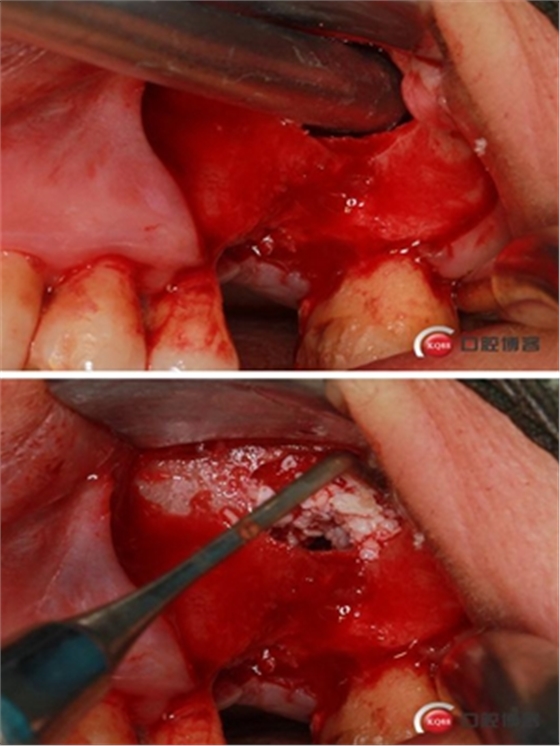

1ml水量便可將頰側(cè)上頜竇膜在還沒有開窗剝離之前就已經(jīng)與上頜竇頰側(cè)骨壁剝離開來,所以此時再在開孔處開窗將不用再擔(dān)心會傷及上頜竇膜。用環(huán)切開窗鉆,將種植機調(diào)成反轉(zhuǎn)模式、轉(zhuǎn)速調(diào)至200-500轉(zhuǎn)之間。

無需全部磨穿,剩余一些骨量既可以。

將骨片撬開并取下。

還沒有進行竇膜剝離,頰側(cè)上頜竇膜已經(jīng)和骨壁有效分離。

擴大窗口,進一步剝離竇膜。

植入骨粉。

骨高度比曲斷片顯示的更低,不利于同期植入,直接縫合。